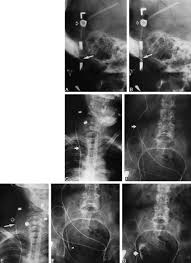

Peritoneal Portion Of Vp Shunt Download Scientific Diagram

The Adult Radiographic Shuntogram American Journal Of Neuroradiology